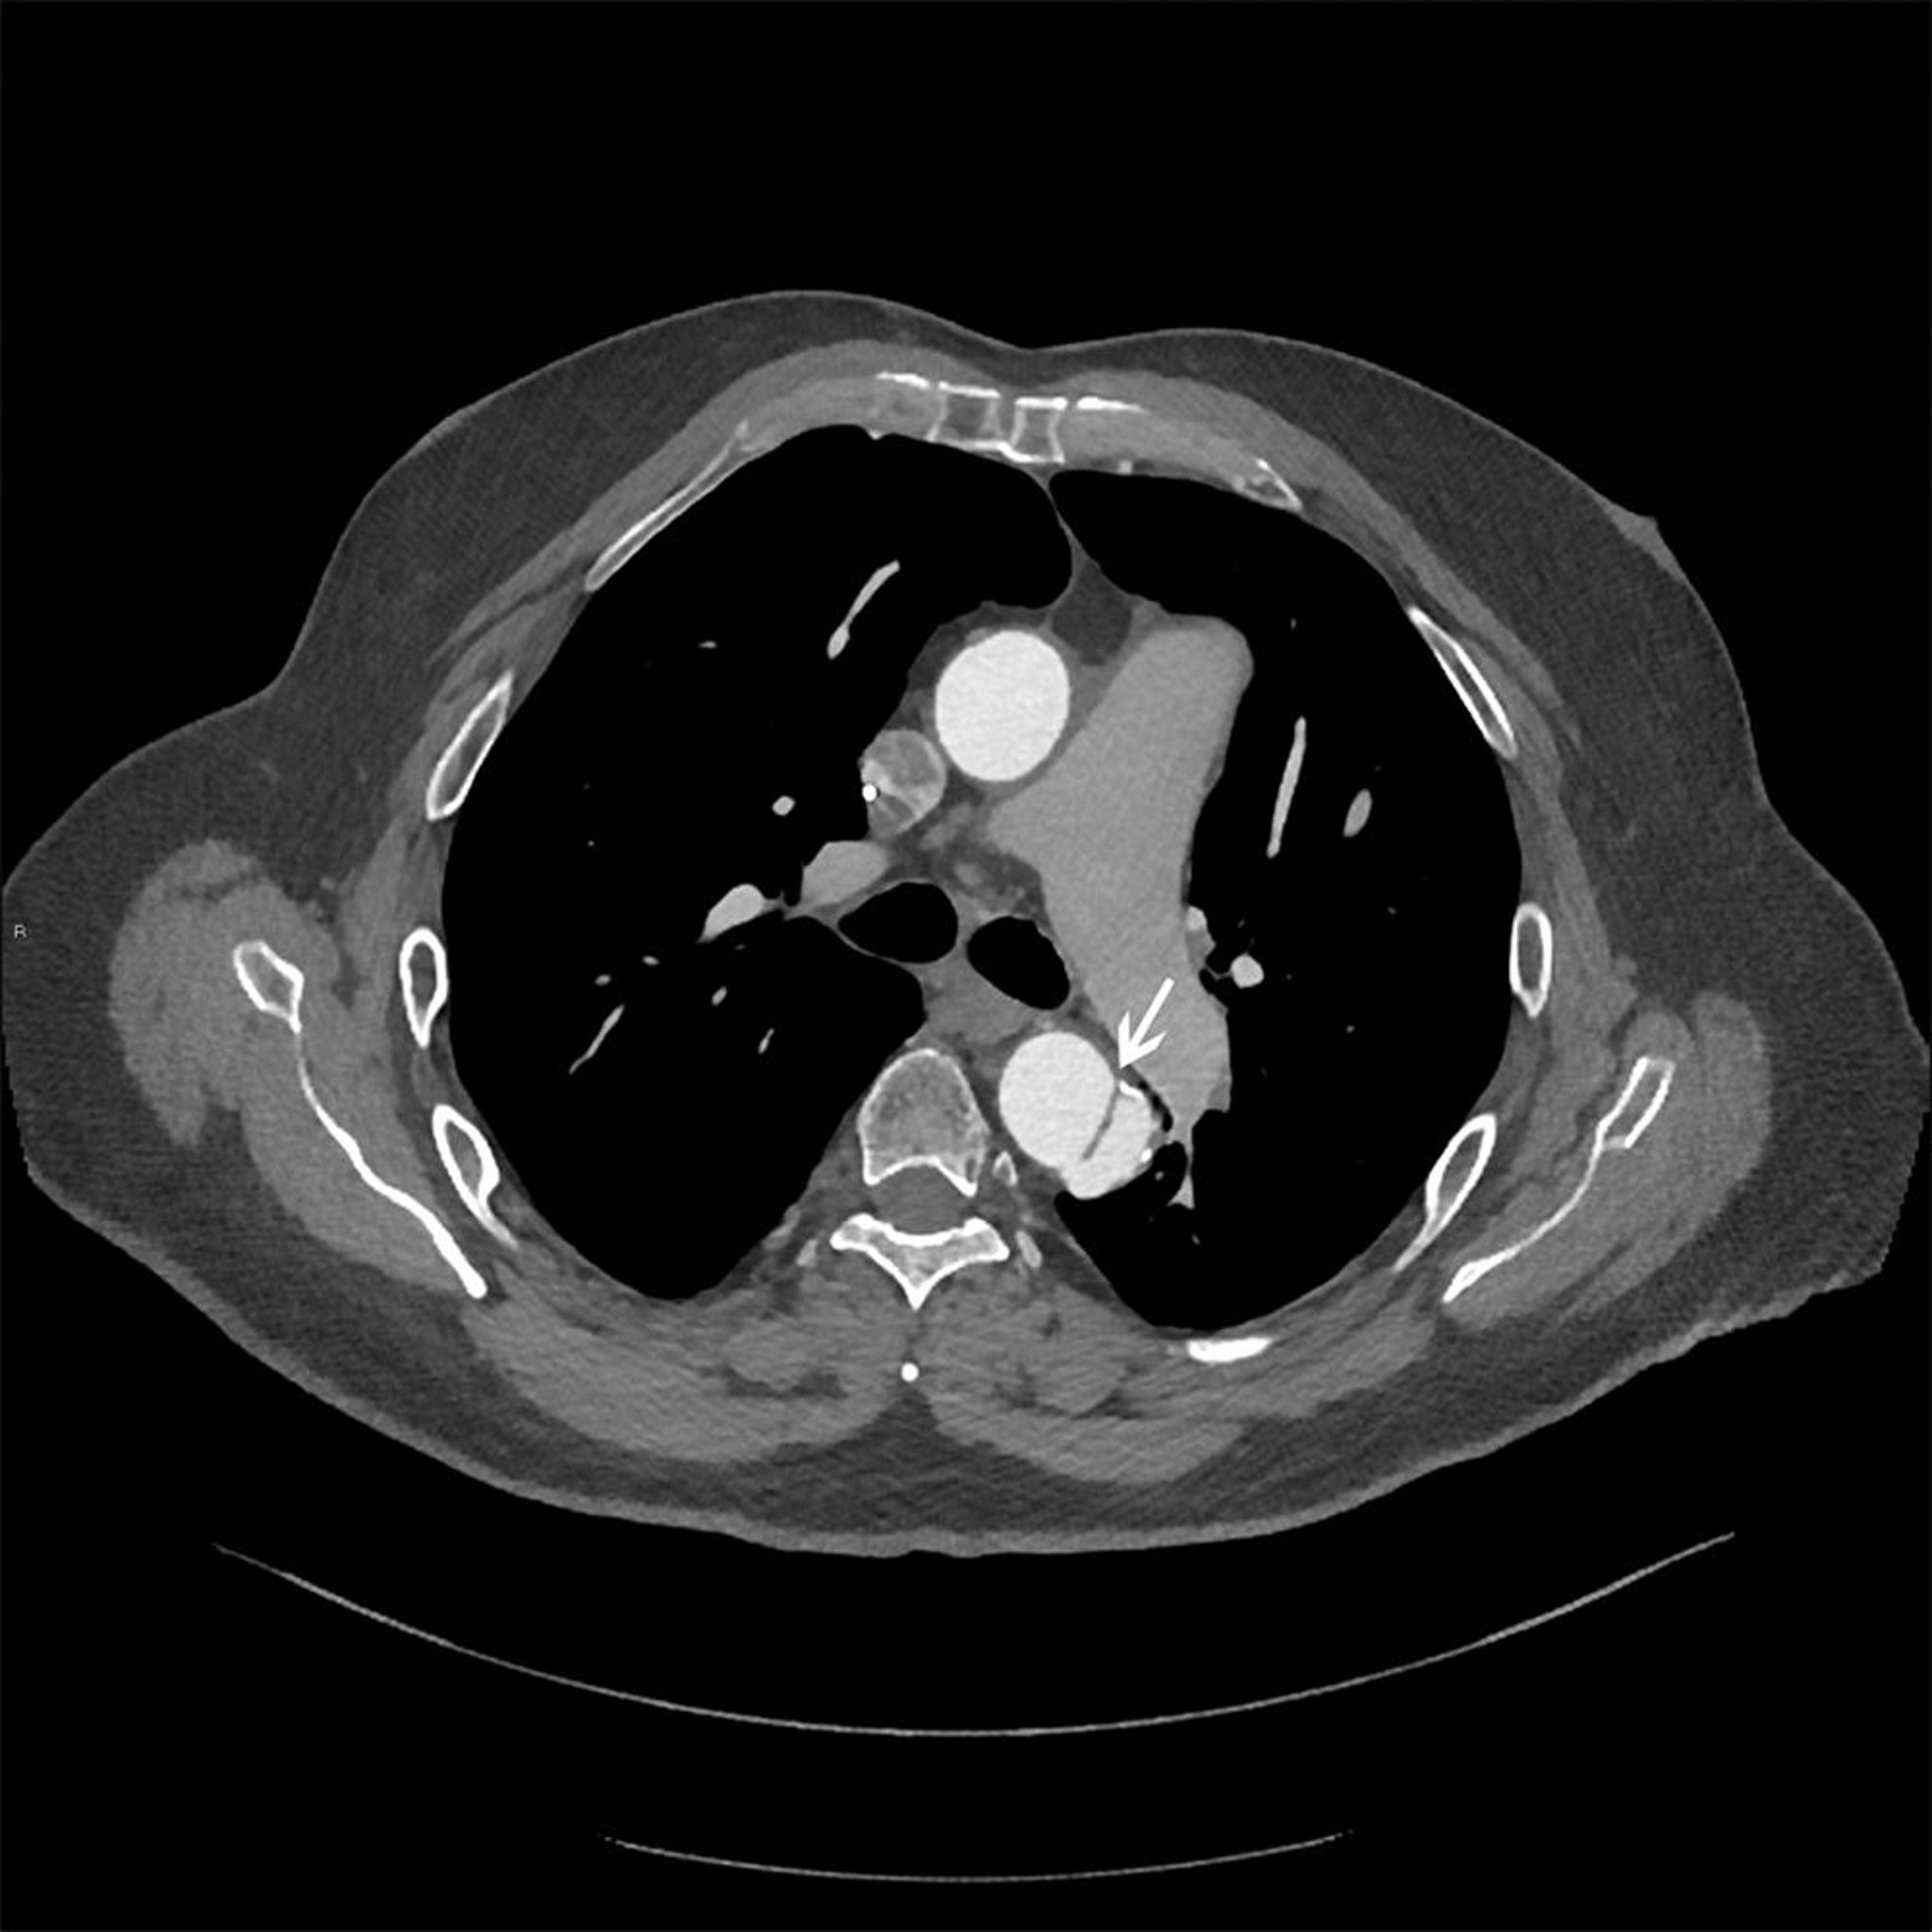

Dissection de l'aorte thoracique (Stanford type B)

Image axiale du lambeau de dissection (flèche blanche) dans l'aorte thoracique descendante.